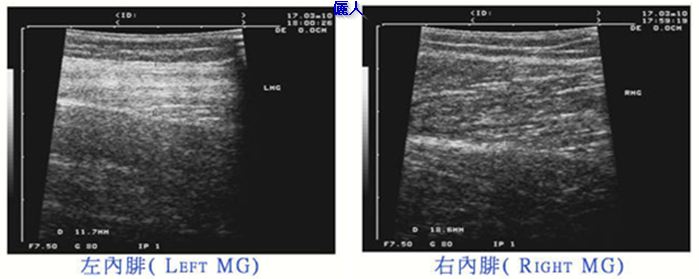

此病例在五年前曾做過小腿切神經手術,左側內腓有萎縮現象,但右側內腓沒什麼萎縮,可以由術前的超音波圖像看出左側內腓的肌肉紋理緻密,變成一片白色,厚度較薄。右側內側是正常的黑白紋理,厚度較厚。術前左側小腿圍是34.5公分,右側是35.5 公分。在我們診所做完小腿肌肉手術及小腿抽脂後小腿變為32公分。